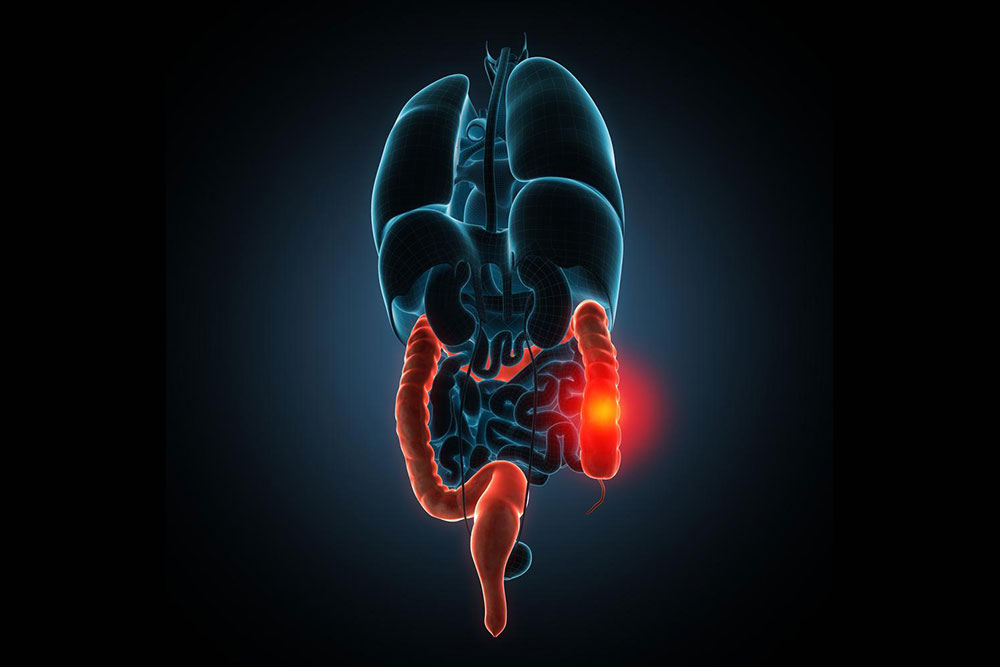

There are ailments one suffers from, whose cause are still a mystery and if one does discover the causes of the ailment, figuring out the treatment would require ounces of patience. One such disorder is Irritable Bowel Syndrome (IBS). The causes of the IBS are unknown, but it is treatable.

IBS cannot be fully cured, instead doctors focus on treating the causes of IBS. So, here are the popular treatments for treating the causes of IBS, which would enable the patients to lead a normal life.

Antispasmodics- Severe abdominal pain is a characteristic symptom of IBS. The pain is excruciating and it can occur in any part of the abdomen. The doctor would prescribe certain antispasmodic drugs that can relieve you from your abdominal pain.